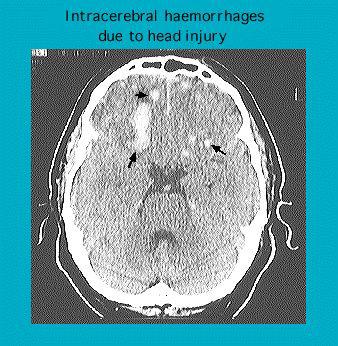

CT scan showing traumatic intracerebral haemorrhage